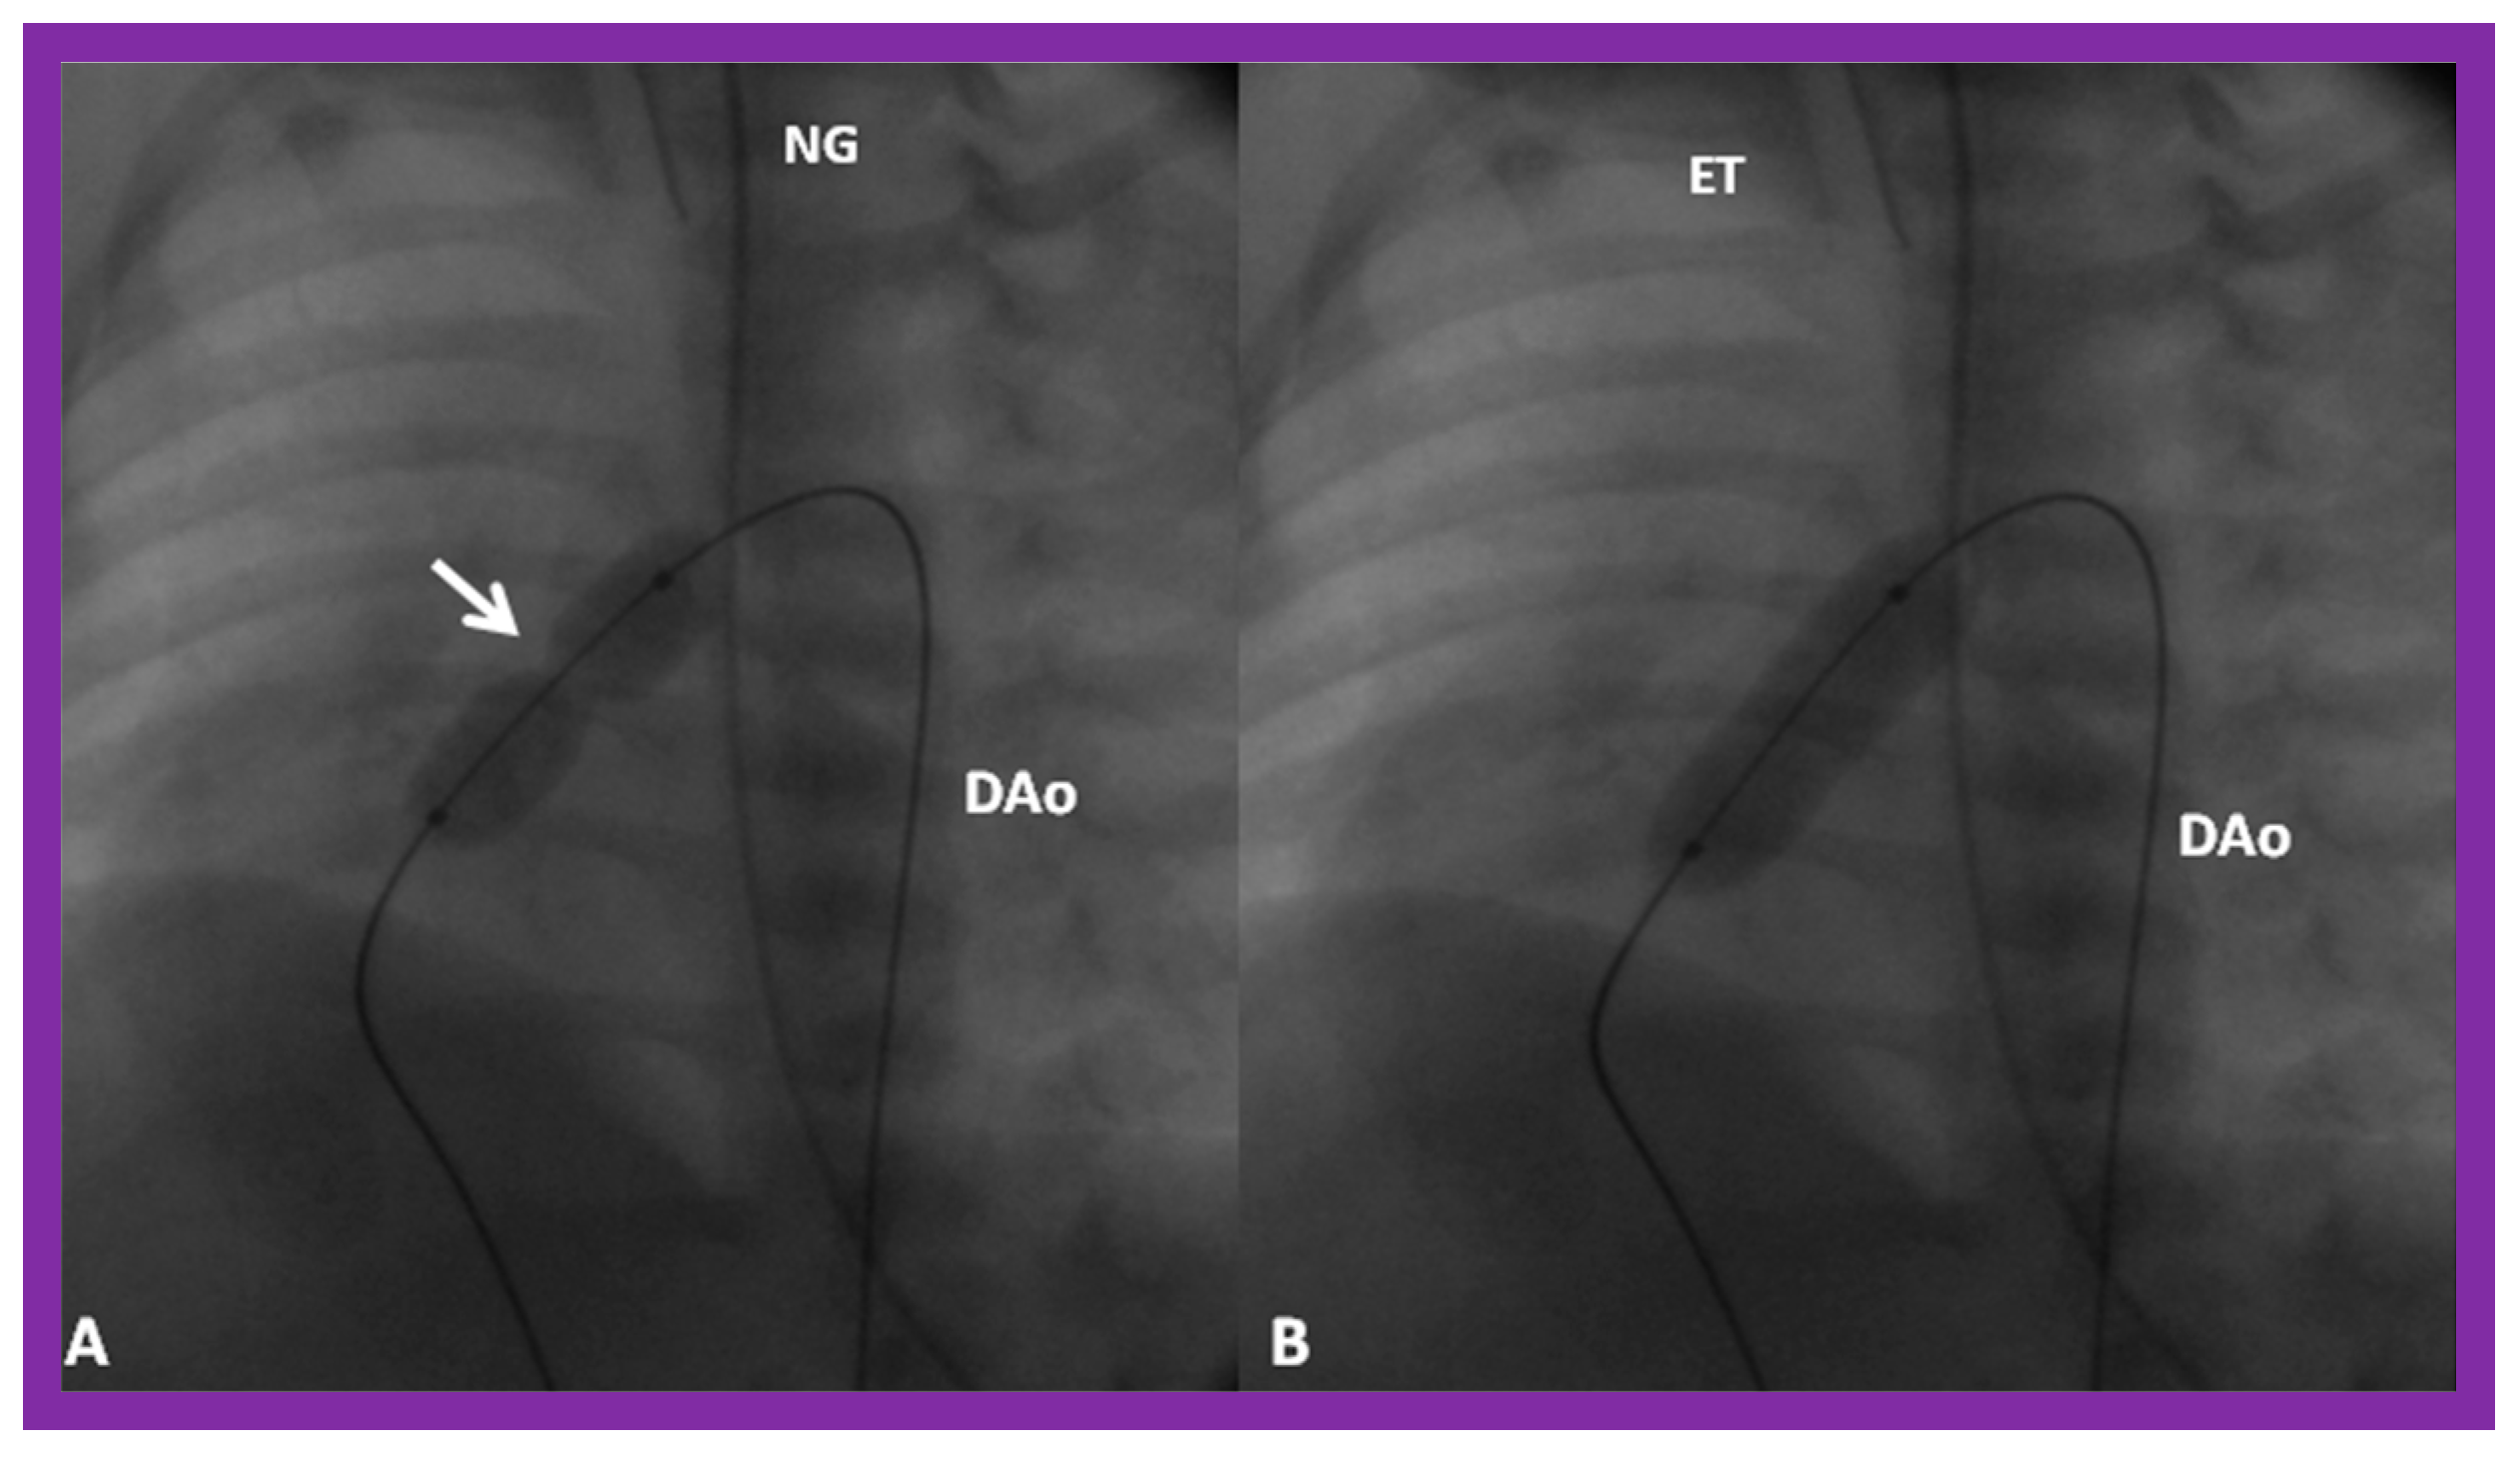

3.3. Aortic Coarctation, Native

Revisit BA in the Neonate and Young Infant